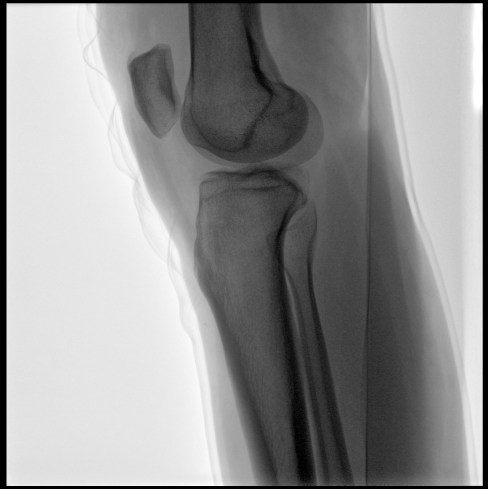

臨床應(yīng)用廣泛,適用于關(guān)節(jié)手術(shù)、創(chuàng)傷手術(shù)、脊柱手術(shù)、疼痛治療等。